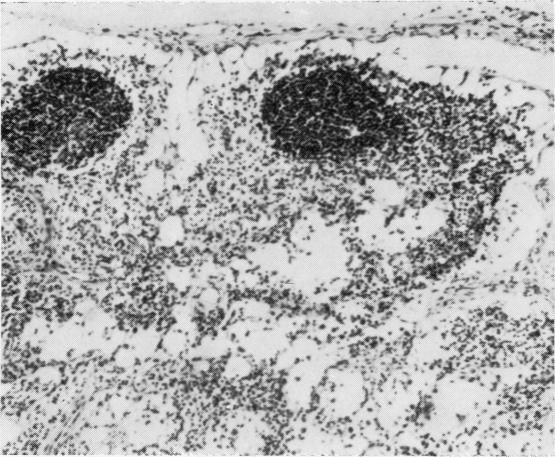

The histopathological appearances of the thymus, lymph nodes, spleen, and gut-associated lymphoid tissue (tonsil, Peyer's patches, and appendix) in cases of the combined immunity-deficiency syndrome are presented. The appearance of tissues remaining after foetal thymic transplants and the effects of such transplants on the morphology of lymph nodes are also discussed. Although thymic appearances are remarkably constant the picture in the lymph nodes and spleen may vary considerably. The tonsils, Peyer's patches, and appendix appear to constitute one lymphoid organ in man, at least with regard to the developmental arrest that may occur in this syndrome.

本文呈现了联合免疫缺陷综合征病例中胸腺、淋巴结、脾脏及肠道相关淋巴组织(扁桃体、派伊尔结和阑尾)的组织病理学表现。还讨论了胎儿胸腺移植后剩余组织的外观以及此类移植对淋巴结形态的影响。尽管胸腺的表现非常一致,但淋巴结和脾脏的情况可能有很大差异。扁桃体、派伊尔结和阑尾在人类中似乎构成一个淋巴器官,至少就该综合征可能出现的发育停滞而言是这样。